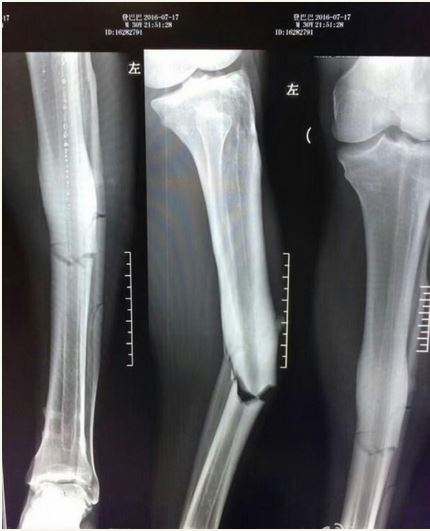

Ba, 31, had netted 14 goals in 18 appearances for Shanghai Shenhua this season but appeared to badly break his leg in a tangle with a Shanghai SIPG FC defender.